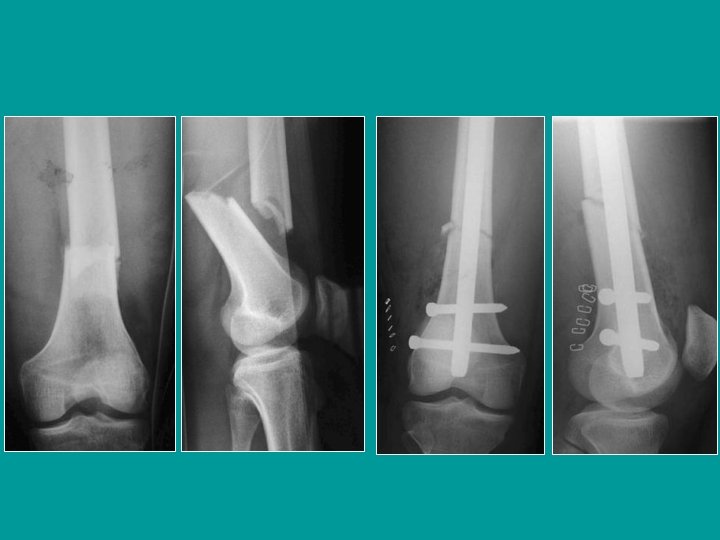

Fractures unicondylienne verticale de Trélat Vissage transversal simple ou plaque

Fractures unicondylienne horizontale de HOFFA Vissage transversal en rappel. Les têtes de vis sont enfouies sous le niveau du cartilage